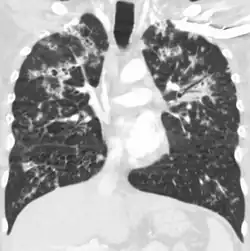

A case of miliary tuberculosis in an 82-year-old woman:

-

X-ray, 13 days after onset, showing bilateral interstitial infiltrates -

CT, 16 days after onset, showing extensive pulmonary parenchymal involvement consisting of irregular septal thickenings with ground-glass areas and centrilobular nodules with a peri-lymphatic distribution -

X-ray, 22 days after onset, showing extensive bilateral reticulo-nodular infiltrates -

Gross pathology of the lung, spleen and kidney, showing micronodules (1–4 mm in diameter) which resemble millet seeds -

Histopathology, showing epithelioid granulomas with multinucleated giant cells and acid-fast bacilli